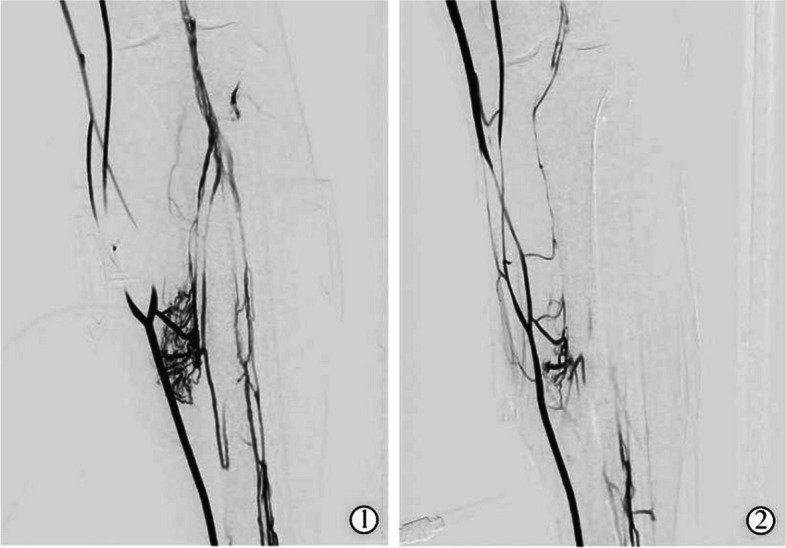

Objective: To evaluate the comparative effectiveness of two distinct balloon pressure band compression regimens on the treatment outcomes for deep vein thrombosis (DVT) and venous blood flow velocity in the lower limbs of patients undergoing anterograde thrombolysis through the superficial dorsalis pedis vein.

Methods: A total of 42 patients diagnosed with DVT were enrolled in the randomized controlled trial. Patients in the control group received balloon pressure band compression positioned 15 cm above the bony landmark of the medial malleolus of the affected limb, with continuous inflation and deflation. On the basis of the control group, a balloon pressure band was also used 15 cm above the bony landmark of the medial malleolus and 10 cm below the midpoint of the patella in the affected limb in experimental group, with rotational inflation at these two sites. The thrombolysis effects and venous blood flow velocity of the lower extremities were compared between the two groups.

Results: The differences in limb circumference and Marder scores of patients in the experimental group were significantly lower than those in the control group, while the detumescence rate and venous patency rate of the affected limbs in the experimental group were significantly higher than those in the control group (P < 0.05). After 30 and 60 min of thrombolysis, femoral and popliteal vein blood flow velocities in the experimental group were significantly higher than those in the control group (P < 0.05). After 45 min post-thrombolysis, the femoral vein blood flow velocity in the experimental group remained significantly higher than that in the control group (P < 0.05), though no significant difference was observed in the popliteal vein blood flow velocity (P > 0.05).

Conclusion: In this study, alternating balloon pressure band compression applied at 15 cm above the bony marker of the medial malleolus and 10 cm below the patellar midpoint to block superficial venous blood flow was found to enhance thrombolysis efficacy and significantly improve venous blood flow velocity in the lower extremities among patients with DVT.